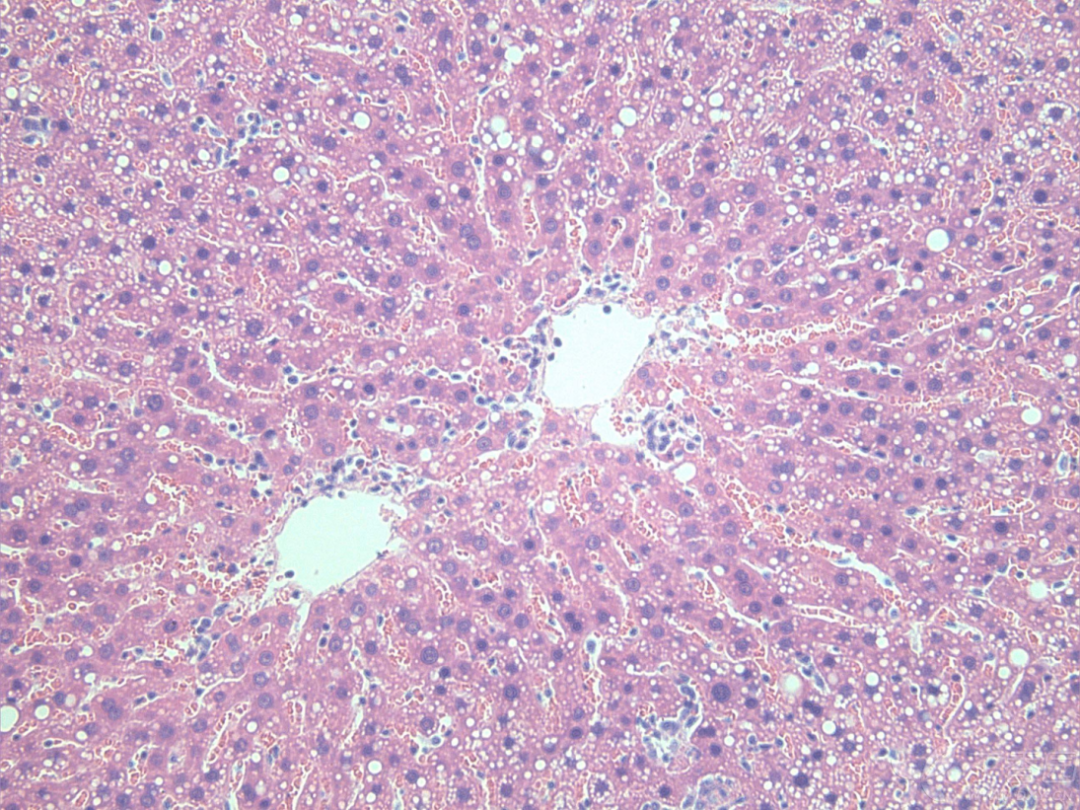

蘇木精-伊紅染色法(HE染色法),作為石蠟切片技術(shù)中的經(jīng)典染色方法,廣泛應(yīng)用于組織學(xué)、胚胎學(xué)及病理學(xué)的教學(xué)與科研中。該方法利用堿性的蘇木精使細(xì)胞核及胞質(zhì)核酸呈現(xiàn)紫藍(lán)色,而酸性的伊紅則讓細(xì)胞質(zhì)與細(xì)胞外基質(zhì)染上紅色。

微信圖片_2025-06-27_173238_284